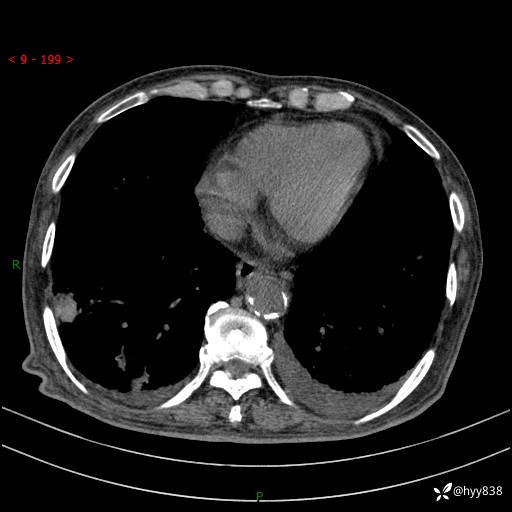

老年男性,间断咳嗽咳痰20余年,加重伴发热1天。呼吸科疑难病例讨论---结果公布

主诉:间断咳嗽咳痰20余年,加重伴发热1天

简要病史:家属代诉患者于20余年前无明显诱因出现咳嗽咳痰,痰为白色泡沫状,未行特殊治疗,不伴胸痛、胸闷、气喘、咳血等不适,1天前上午患者无明显出现发热,查体温39℃,伴咳嗽,咳痰无力,自行予以物理降温对症治疗,今晨2点左右再次出现发热,体温达40℃,自行服用复方氨酚烷胺对症治疗,凌晨3点左右复测体温38.2℃,现患者为求进一步诊治于今日就诊于我院门诊,行胸部CT提示双肺感染,遂以“肺部感染”收入我科。 患者本次起病来精神、食欲、睡眠欠佳,体力下降,体重无明显变化。

辅助检查:CT

胸部CT平扫